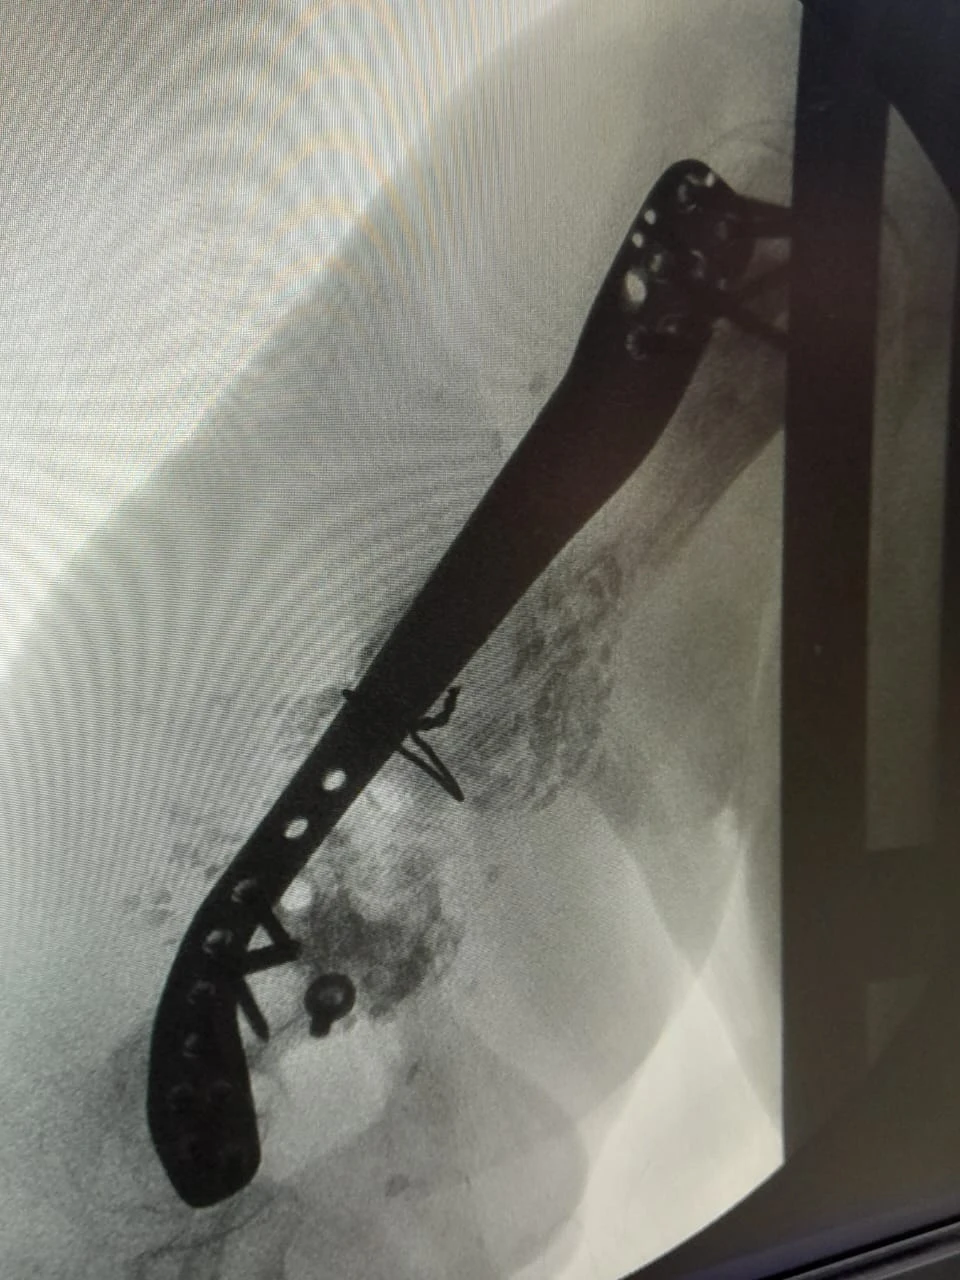

No último dia 28, a equipe de Ortopedia e Traumatologia da Santa Casa de Ponta Grossa realizou um procedimento cirúrgico inédito na região dos Campos Gerais, que consiste na correção de ossos em situações de fraturas. Neste caso, a paciente em questão fraturou o úmero (osso superior do braço), passou por diversas cirurgias em outras instituições, porém sem obter sucesso. O cirurgião Dr Carlos Miers explica a dificuldade para a realização do procedimento: “a cada cirurgia realizada a quantidade de osso disponível no braço era menor, e quando a paciente chegou até mim ela já tinha o úmero direito muito menor que o esquerdo, e com um defeito ósseo grande." A primeira etapa do tratamento consistiu em tratar a infecção, após isso foi necessário fazer um transporte ósseo com fixador externo, utilizado pela paciente durante 2 anos. Em seguida foi necessário estabilizar e fixar o úmero da parte superior até a inferior, porém não havia placa/haste disponível no mercado que supria a necessidade desta paciente “aí que começa a singularidade deste procedimento, nós em parceria com a empresa Neoortho, desenhamos e desenvolvemos uma placa personalizada especifica para a anatomia desta paciente”, explica o profissional. O projeto de personalização da placa foi realizado utilizando tecnologia de ponta através e modelos computacionais extraídos de tomografia, simulações mecânicas em elementos finitos para garantir que o material não iria falhar durante o tratamento: “após diversos testes chegou-se a versão final da placa que foi instalada na paciente durante a cirurgia”, complementa o Dr Carlos. Participaram da cirurgia os profissionais Dr Carlos Miers e o Dr Rodrigo Favaro, o procedimento foi realizado no centro cirúrgico da Santa Casa, durou 4 horas e foi um sucesso. A Instituição que é referência para 28 municípios vem traçando estratégias para cumprir sua missão de acolher e tratar o paciente respeitando sua individualidade, proporcionando uma experiência em saúde com ética, segurança, tecnologia e resolutividade. [gallery size="medium" ids="137648,137649,137650"]